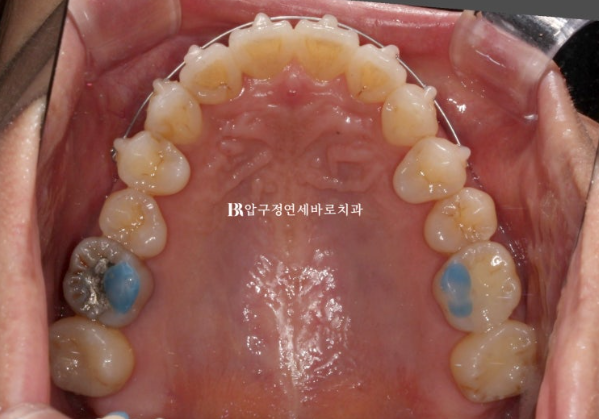

The blue resin on the molars is a bite block, also called an occlusal pad.

It temporarily raises the bite so that the front teeth do not touch.

It is not commonly used in front-tooth partial orthodontic treatment, but we proceeded with it considering the patient’s situation and the tight schedule.

24.01